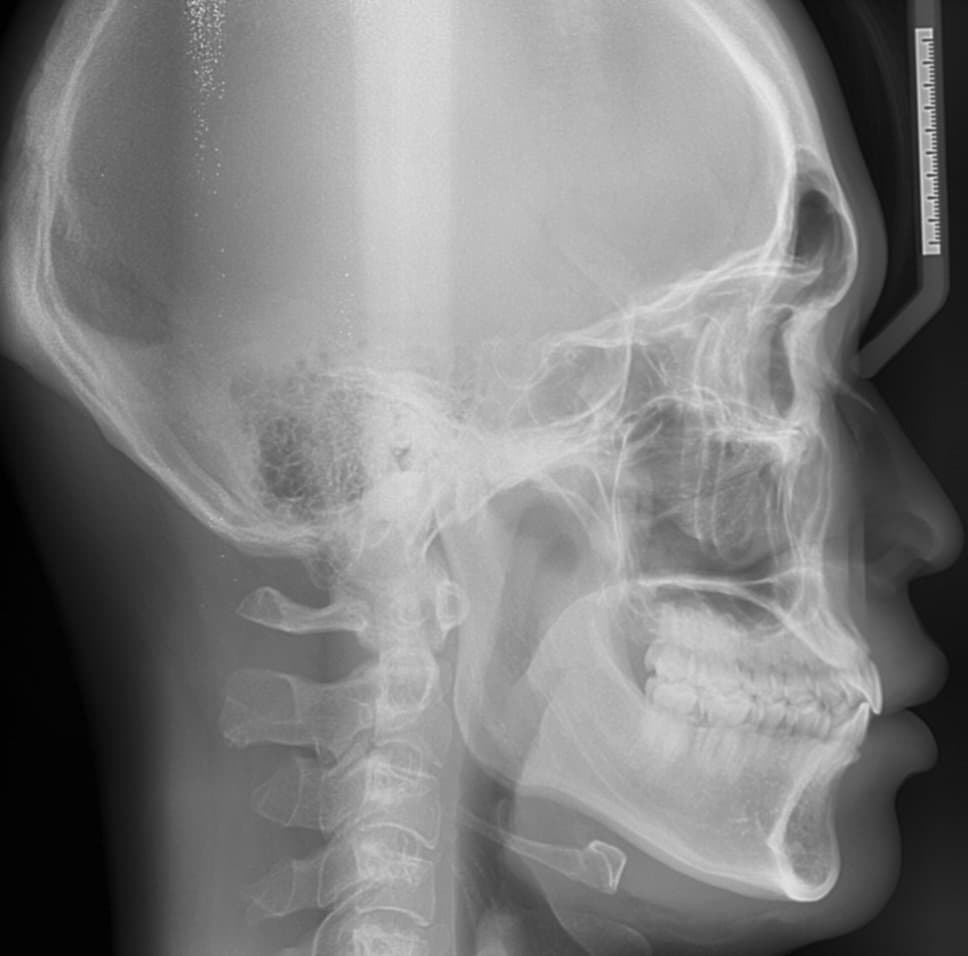

1. 해당 정보를 알기 위해서는 계측점에 따른 수치가 필요합니다. 현재 ceph. 사진에 계측점에 따른 값이 나와 있지만 어느점을 기준으로 했는지에 따라 다르므로 계측을 직접해보아야 합니다.

2. 현재 수치만으로 보았을 때는 하악골이 과다하게 발달 한 것보다는 상악골이 덜 발달했을 가능성이 있어 보입니다.

3. 긴편에 속하지 않습니다. 상악골이 덜 발달 되어 길어보이는 것으로 보입니다.